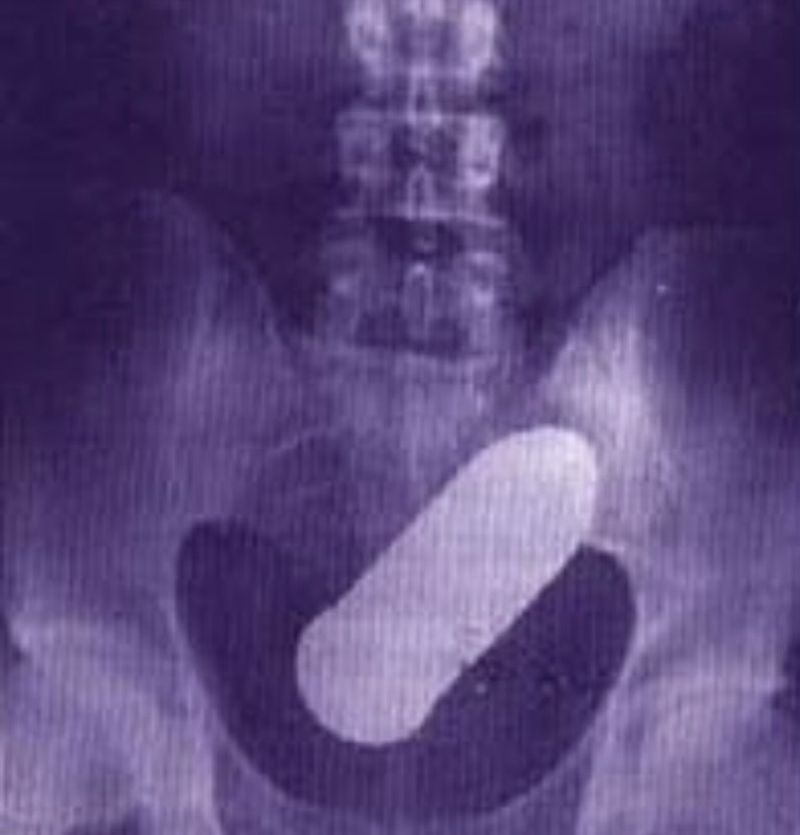

2 din 4 | Radiografia pacientului de 24 de ani

Obuzul de 20 de centimetri era perfect funcțional, potrivit Daily Mail .

Medicii nu își explică cum a ajuns obuzul de artilerie din Primul Război Mondial, de 20 de centimetri, în fundul pacientului.

Personalul și pacienții au fost evacuați din Spitalul Rangueil, iar în jurul unității de urgență a fost instituit un perimetru de securitate, înainte ca obuzul ascuțit din 1918, care avea aproape 20 de centimetri lungime și puțin peste 2,5 centimetri în circumferință, să fie declarat sigur.